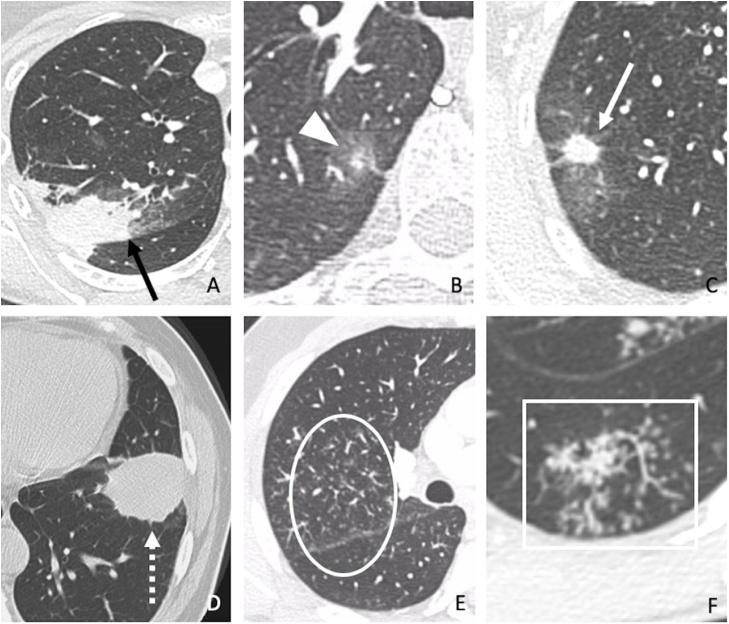

Etiological profile and main imaging findings in patients with granulomatous diseases who underwent lung biopsy.

Granulomatous Lung Diseases (GLD) encompasses a wide range of infectious and non-infectious conditions characterized by chronic inflammatory response. However, different GLD may share similar imaging findings. In this context, the purpose of this study was to outline the etiological profile and their imaging features in patients with GLD who underwent lung biopsy.

Thirty-eight of 75 (50.7%) patients were women with a mean age of 59 ± 39 years. Infection was the most common cause of GLD (47/75, 62.7%) and (27/75, 36%) was the most prevalent etiology. Nodular pattern was the most common imaging feature in histoplasmosis cases (25/27, 92.6%), whereas it occurred in half of cases (24/48) of GLD of other causes (p < 0.05). Among patients with tuberculosis, the second etiology of GLD in our study population, the most common imaging pattern was centrilobular micronodules (3/7, 42.9%), significantly more frequent than in other causes of GLD (6/68, 8.8%). Interreader agreement in detecting imaging features was almost perfect (κ = 0.88-1.00), except the nodular pattern, which had substantial agreement (κ = 0.73).

In our study population, the main etiologies found in patients with granulomatous disease who underwent lung biopsy were fungal or mycobacterial disease, specially histoplasmosis and tuberculosis, and nodular pattern with focal distribution was the most common imaging finding which was detected with substantial interreader agreement.